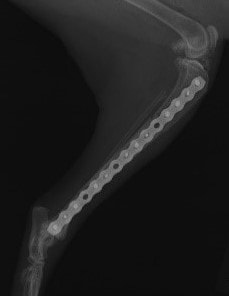

トイプードル 右遠位橈尺骨短斜骨折のALPSによる内固定

当院ではAdvanced Locking plate system(ALPS)と、Locking compression plate system(LCPS)という骨接合法で骨折症例の治療を行っています。

Advanced Locking Plate System

従来型のプレートのように広い面積で骨と接するプレートを用いて固定を行った場合、プレート下の骨はプレートとの接触面において血行が絶たれ壊死し、それがリモデリングされると骨密度が低下する。この骨密度の低下防ぐために、骨折部局所への血行を温存することの重要性が近年改めて認識されるようになってきている。Advaed Locking Plate System (ALPS)は従来型のプレートシステムの欠点を改良し、より使いやすく、より骨への血行を阻害しないようにというコンセプトで作られた。

Advanced Locking Plate System の特徴

- 骨への血行障害は最小限である

- 上下左右にベンディング可能でより3次元的な成形が可能

- すべての部位においてプレート強度は均一である

- ロッキングスクリューと圧着型スクリュー(皮質骨スクリュー)の双方が使用できる

- ダイナミックコンプレッション機能

- 生体親和性の高いチタン製

- トイ犬種から馬まで応用できるサイズ展開がある